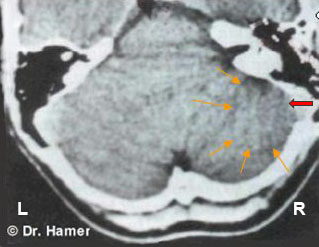

THE BIOLOGY OF THE BRAIN

Dr. Hamer is the first to investigate the cause of diseases by taking the brain into close account. The brain controls all processes in the body. By comparing his patients' brain CT scans with their medical records and their personal histories, he found that an emotional trauma or “conflict shock” (DHS as he termed it) leaves a visible mark in precisely the same area of the brain that controls the disease process. Based on the study of tens of thousands of cases, he discovered that the psyche, the brain, and the body constitute a biological unit, encoded with Biogical Special Programs to secure survival. Dr. Hamer established that the brain acts as a mediator between the psyche and the body, with both receiving and transmitting functions. He identified the brain as the biological control station from where these age-old emergency programs are directed and coordinated.

Every so often the HH is also visible on an organ CT, which makes the brain-organ correlation strikingly evident.

The first step was to analyze Anna's brain scan in order to identify what type of conflicts were involved. Among several others, the brain CT revealed two “hearing conflicts” (“I don't want to hear this!”), visible as Hamer Foci in the areas of the cerebral cortex that control the right and left inner ear.